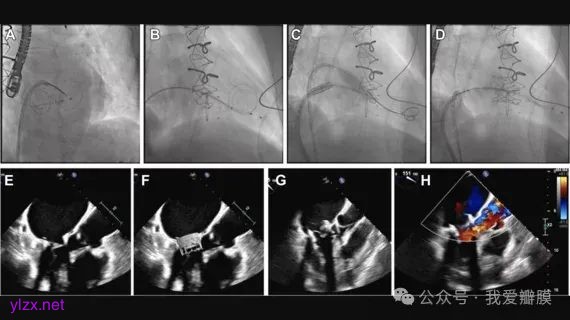

BATMAN 技术的原理精妙而独特,它巧妙地运用球囊的力量,对二尖瓣前叶进行精准改良,从而有效预防 LVOT 阻塞的发生。在操作过程中,医生首先需要凭借丰富的经验和精湛的技术,将一根细细的伙伴丝通过 7F 护套小心翼翼地推进左心室。这一步骤犹如在黑暗中寻找精准的靶点,需要医生高度集中注意力,确保伙伴丝准确无误地到达指定位置 。紧接着,球囊被缓缓送入,精准定位在二尖瓣前叶处。随后,医生会根据患者的具体情况,对球囊进行适当的扩张。这一过程需要医生精确控制球囊的扩张力度和范围,如同在雕琢一件珍贵的艺术品,既要保证对二尖瓣前叶进行有效的改良,又要避免对周围心脏组织造成不必要的损伤。

二尖瓣前叶在球囊的作用下,其形态和结构发生了微妙而关键的改变,从而成功降低了 LVOT 阻塞的风险。这一过程中,医生需要时刻关注患者的生命体征和心脏的各项指标,根据实时反馈调整操作策略,确保手术的安全和有效 。与传统治疗技术相比,BATMAN 技术具有诸多显著的优势。它的操作相对更加简便,大大缩短了手术时间,减少了患者在手术台上的痛苦和风险。其学习曲线较为平缓,使得更多的医生能够较快地掌握这一技术,为更多患者提供优质的治疗服务 。而且,BATMAN 技术的安全性和有效性得到了充分的验证,为心脏病患者带来了更为可靠的治疗选择。